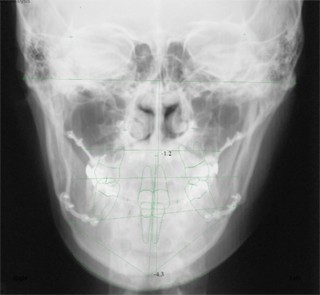

主訴:顎の歪み

診断名:骨格性下顎左方偏位

年齢:24歳

使用した主な装置名:TPB、マルチブラケット装置

抜歯/非抜歯および抜歯部位:非抜歯

治療期間:動的処置1年6か月、経過観察3年

費用の目安:保険適応 自己負担金として30~50万

リスク、副作用:外科手術によるリスク、マルチブラケット治療に伴う歯根吸収など偶発症が発生するリスクがある。

極めて強い側方変位を認めます。前後的・垂直的な問題は見られません。大きなズレであれば、外科的に骨のズレを改善する治療が選択されます。横断的な問題はその他の不正咬合と比較して、解決がかなり難しい事が多いです。治療後の後戻りが頻繁に見られる不正咬合ですので、外科矯正での改善が望ましい場合も多いでしょう。

このケースでは、外科手術は、上顎の傾斜の改善をLeFort1にて、下顎の正中の改善をSSROにて行いました。